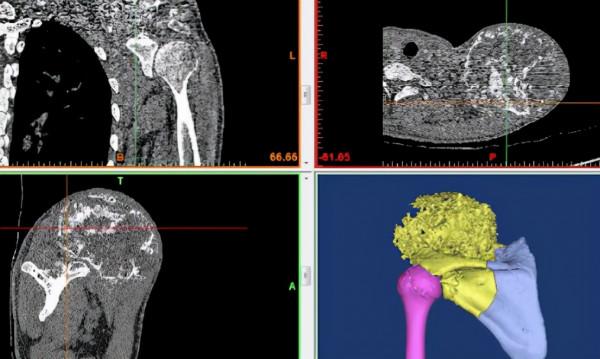

經過規範化新輔助化療後,肖建如團隊為小杰實施了腫瘤enbloc完整切除,手術歷時8個多小時。手術中根據3D列印導板引導精確截骨,3D列印假體重建肩關節,腫瘤達到區域性徹底切除,希望可以達到良好的區域性控制,肩關節的功能也能夠保留一部分。